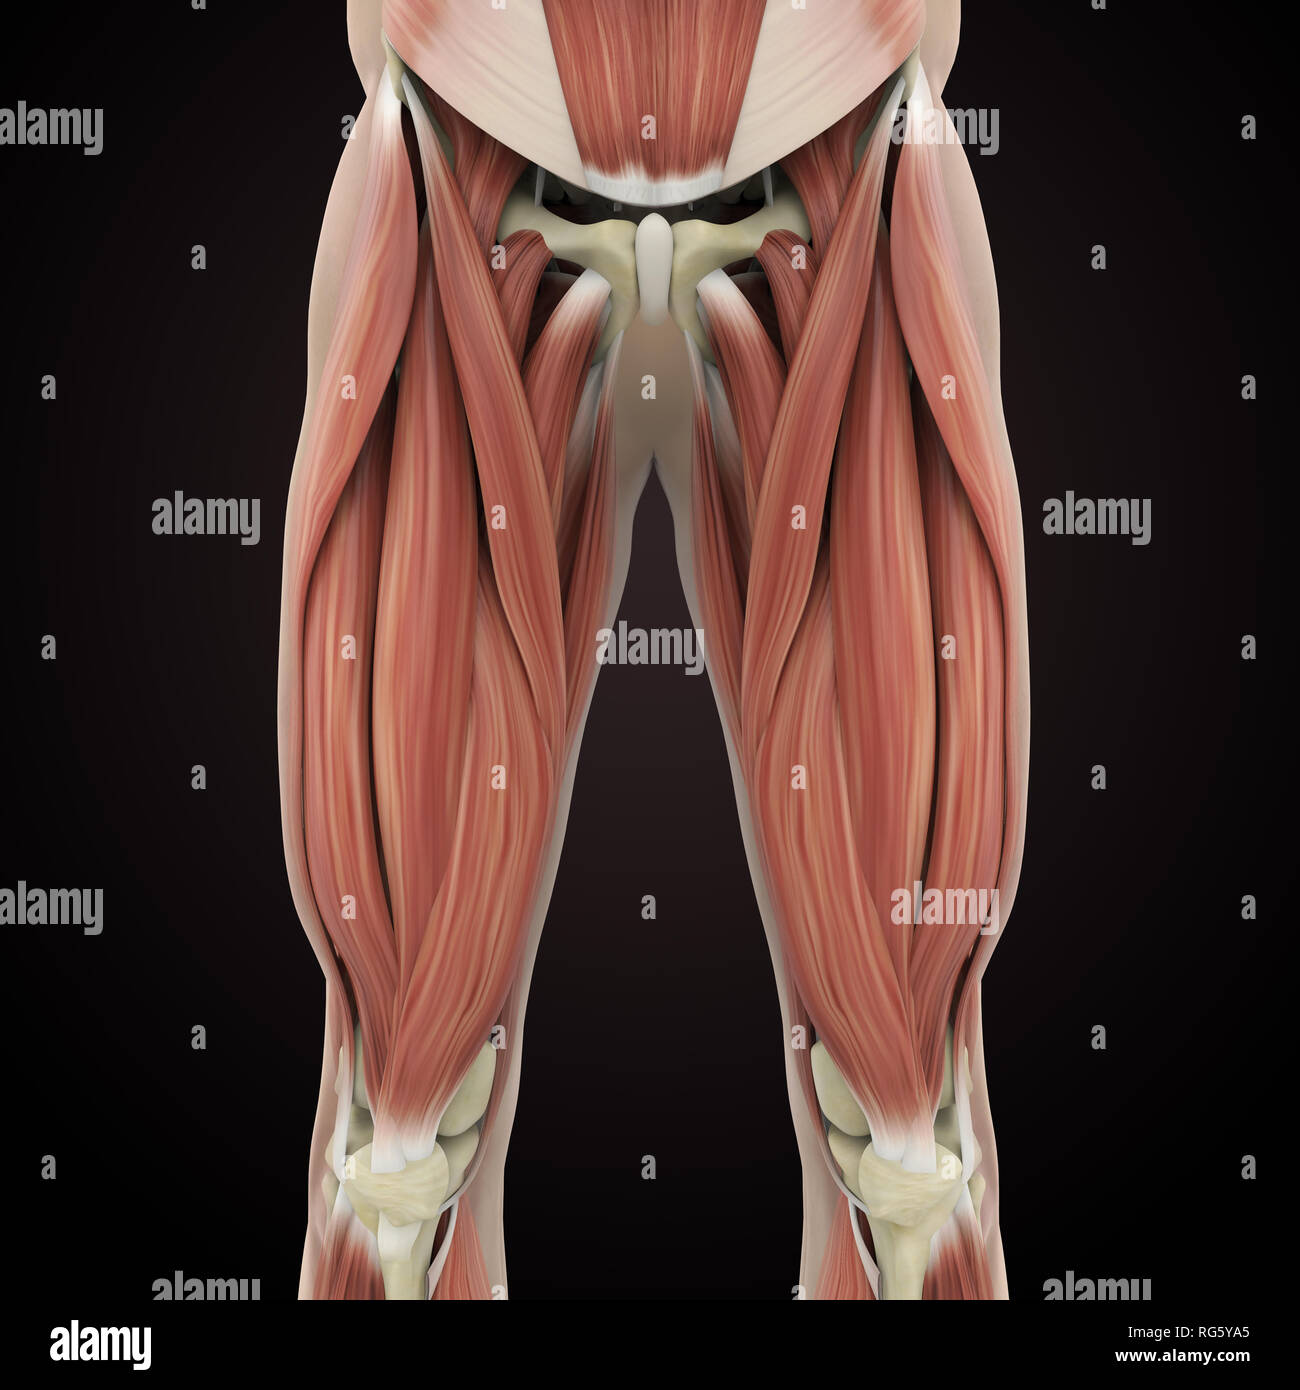

Anatomie des muscles des jambes supérieure Banque D'Imageshttps://www.alamyimages.fr/image-license-details/?v=1https://www.alamyimages.fr/anatomie-des-muscles-des-jambes-superieure-image233700493.html

Anatomie des muscles des jambes supérieure Banque D'Imageshttps://www.alamyimages.fr/image-license-details/?v=1https://www.alamyimages.fr/anatomie-des-muscles-des-jambes-superieure-image233700493.htmlRFRG5YA5–Anatomie des muscles des jambes supérieure